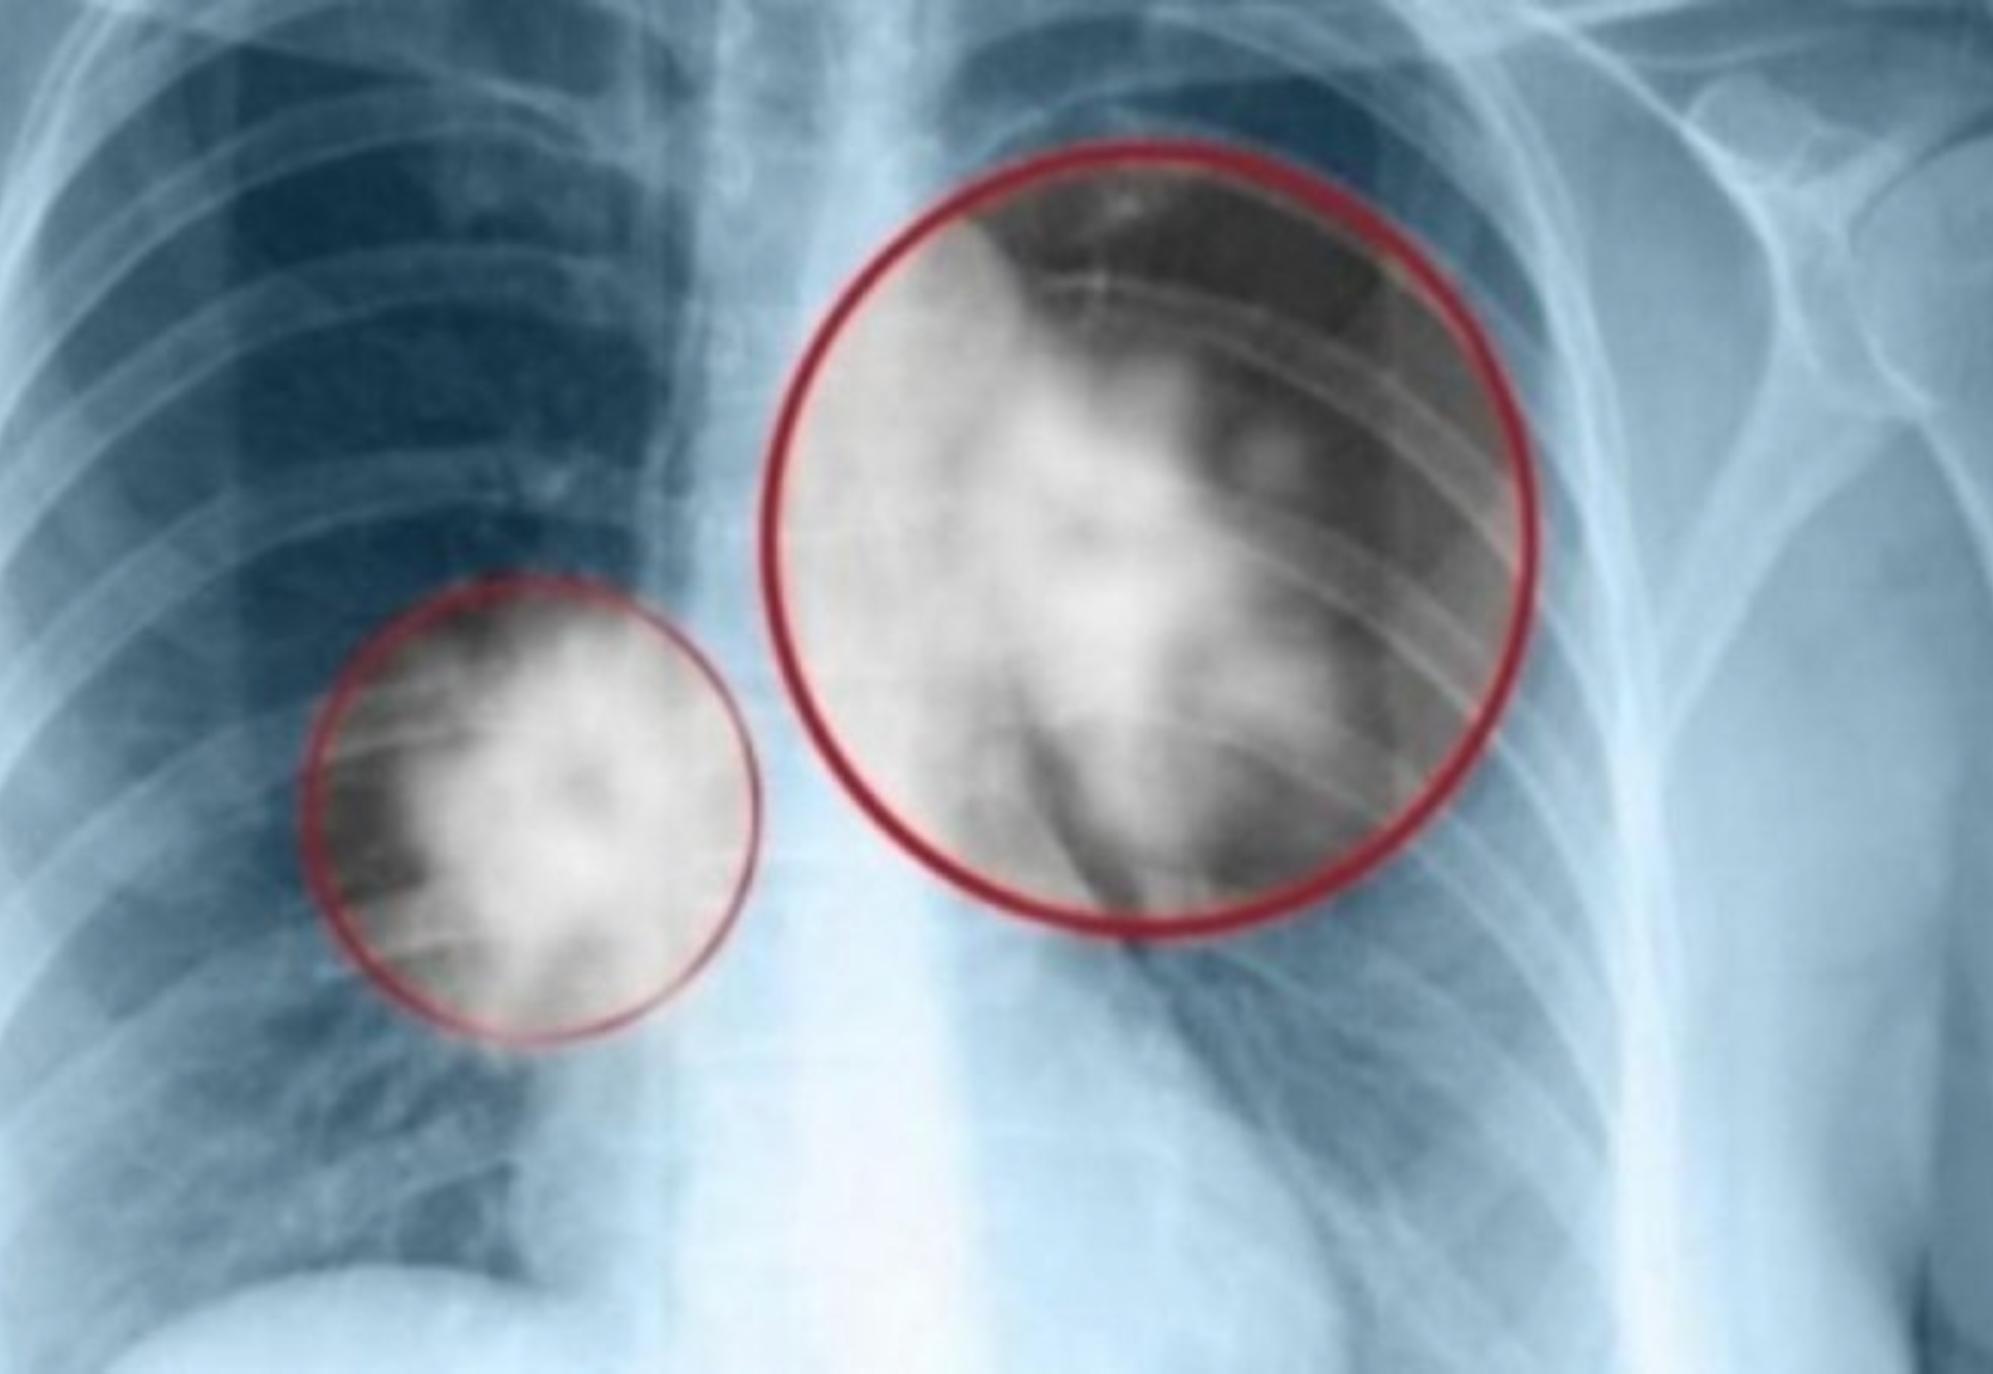

Συνεχής βήχας

Ο συνεχής βήχας είναι ένα από τα συμπτώματα μιας ασθένειας των πνευμόνων, που μπορεί να σχετίζεται με άλλα σημάδια όπως:

-Στο μεταγενέστερο στάδιο, ο καρκίνος των πνευμόνων μπορεί να προκαλέσει αιμόπτυση και δύσπνοια.